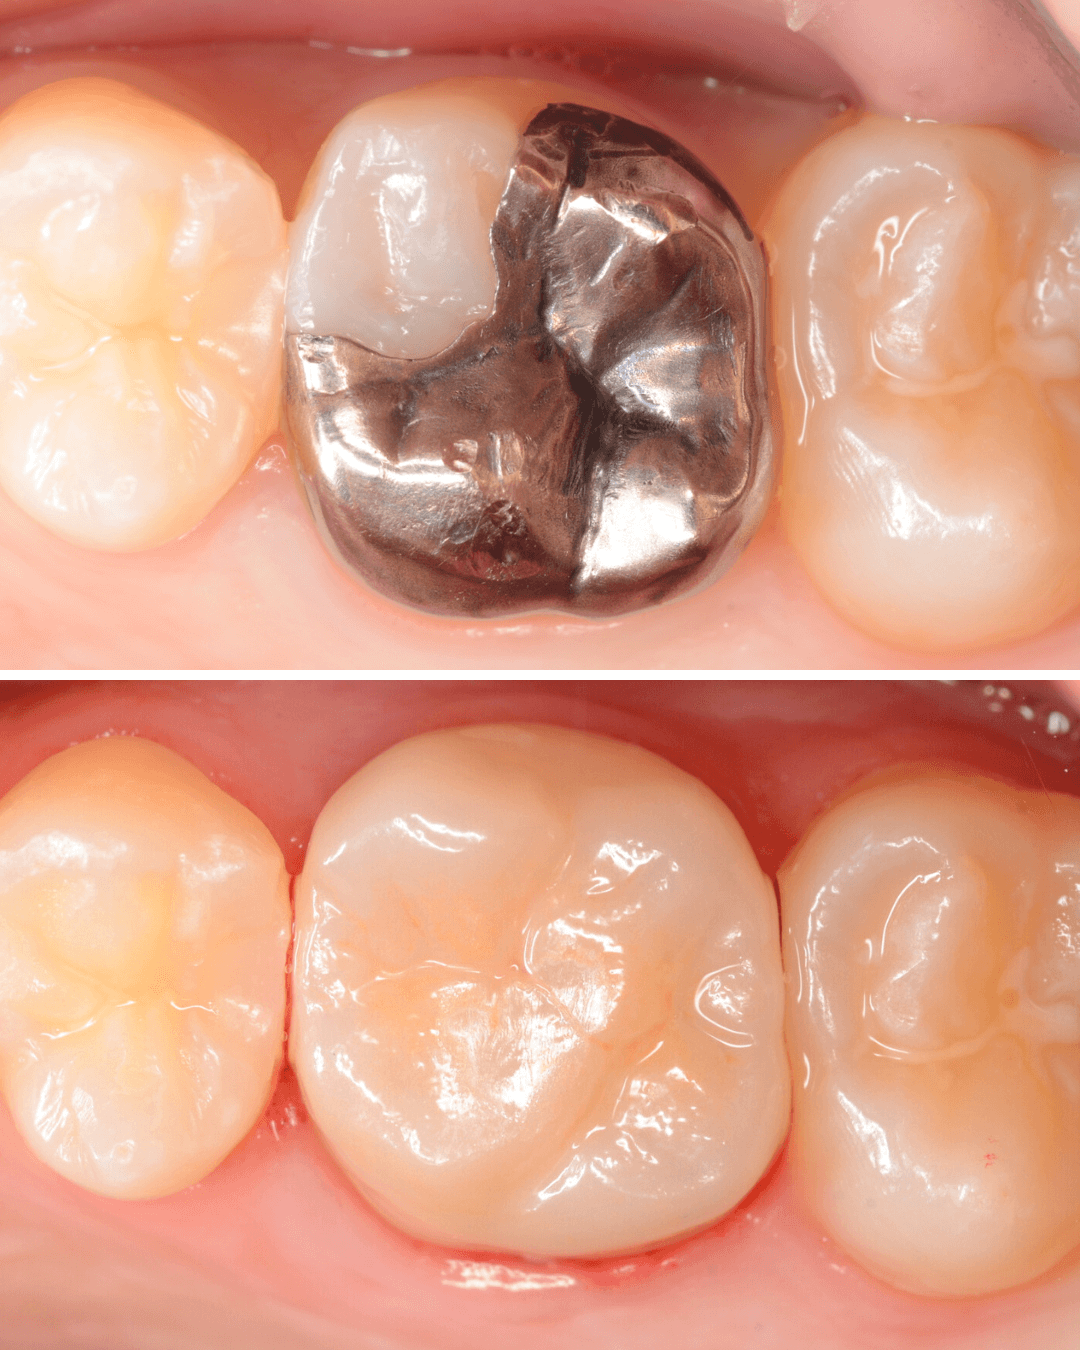

治療前後の比較写真になります。

「上の奥歯の銀歯を白くやり替えたい」というご希望の患者さんです。

検査の結果、再製に問題なさそうでしたので、ジルコニア・クラウンで再製作する治療を進める事になりました。

メタル・クラウンを外すと、奥の歯の虫歯が見つかりました。

set後の写真です。

患者さんにも満足していただける仕上がりになりました。